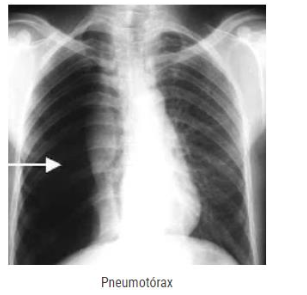

De uma maneira simples, um quadro de pneumotórax ocorre quando há uma lesão da pleura e em consequência disso, o ar, que deveria estar apenas no dentro do pulmão, começa a vazar para a cavidade torácica. Marque a alternativa que agrupa sintomas que identificam/sugerem um quadro de pneumotórax:

Enunciado 3699792-1

Fonte: https://www.mdsaude.com/pneumologia/pneumotorax acesso em 25 de abril de 2024.